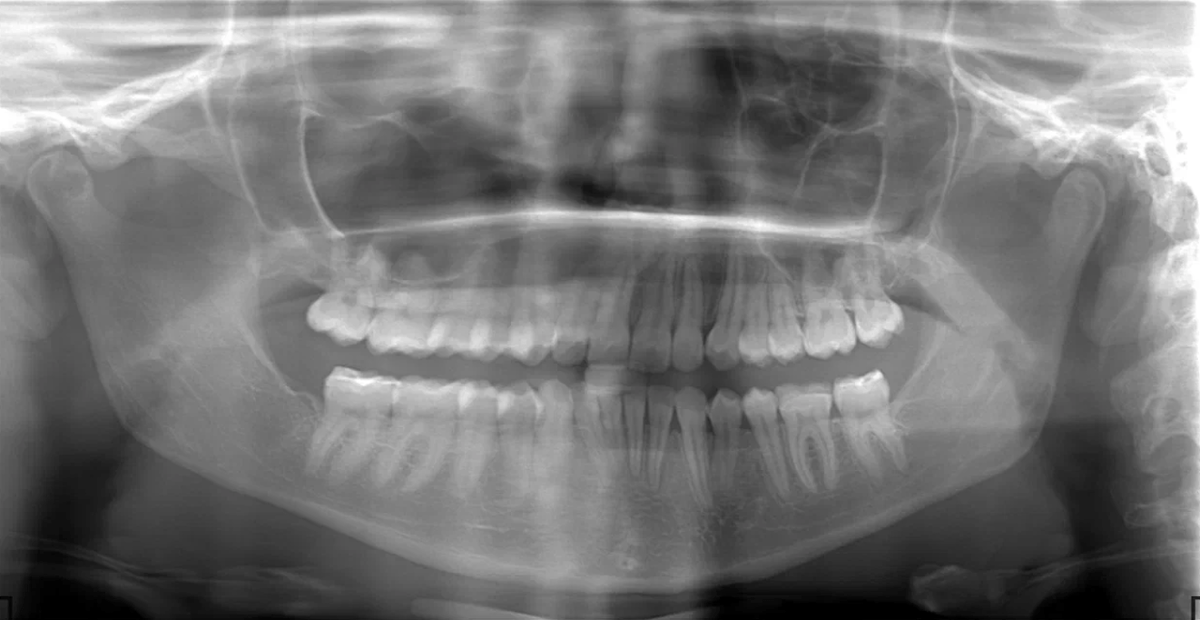

Это основной метод рентгенодиагностики в стоматологии, который помогает обнаружить даже те проблемы, о которых пациент пока не догадывается.Ортопантомограмма (ОПТГ) — это обзорный рентгеновский снимок, на котором одновременно видны обе челюсти, все зубы, корни и окружающая кость. Прицельный рентген показывает только один или два зуба — и не даёт полной картины. Пример: вас беспокоит «шестёрка», но рядом с ней может быть скрытый кариес на «пятерке», воспаление у соседнего корня или киста, не вызывающая боли.

Это основной метод рентгенодиагностики в стоматологии, который помогает обнаружить даже те проблемы, о которых пациент пока не догадывается.Ортопантомограмма (ОПТГ) — это обзорный рентгеновский снимок, на котором одновременно видны обе челюсти, все зубы, корни и окружающая кость.

Панорамный снимок позволяет врачу:

• оценить скрытые воспаления;

• увидеть состояние зубов мудрости;

• проверить плотность и объём костной ткани;

• понять, как расположены корни и зачатки зубов.